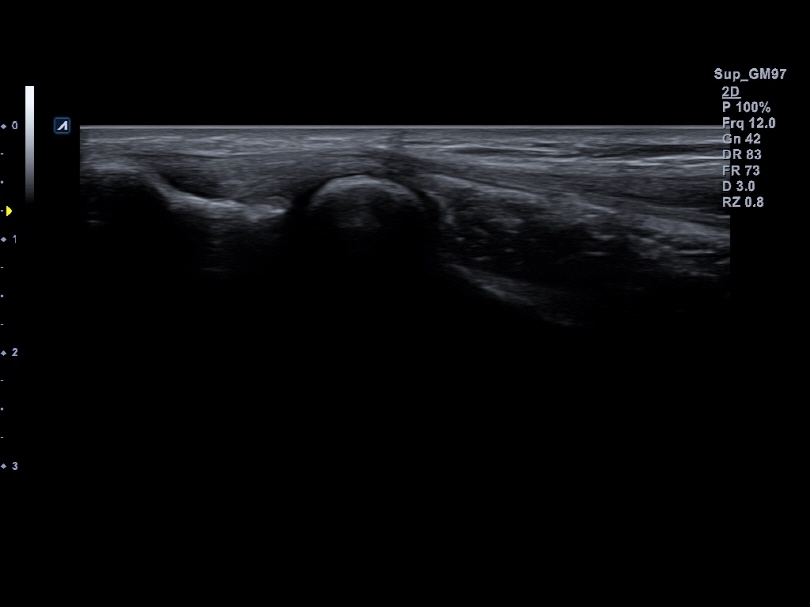

IO8-17T

High frequency hockey stick (8-17MHz)

Application:

Small Parts, MSK